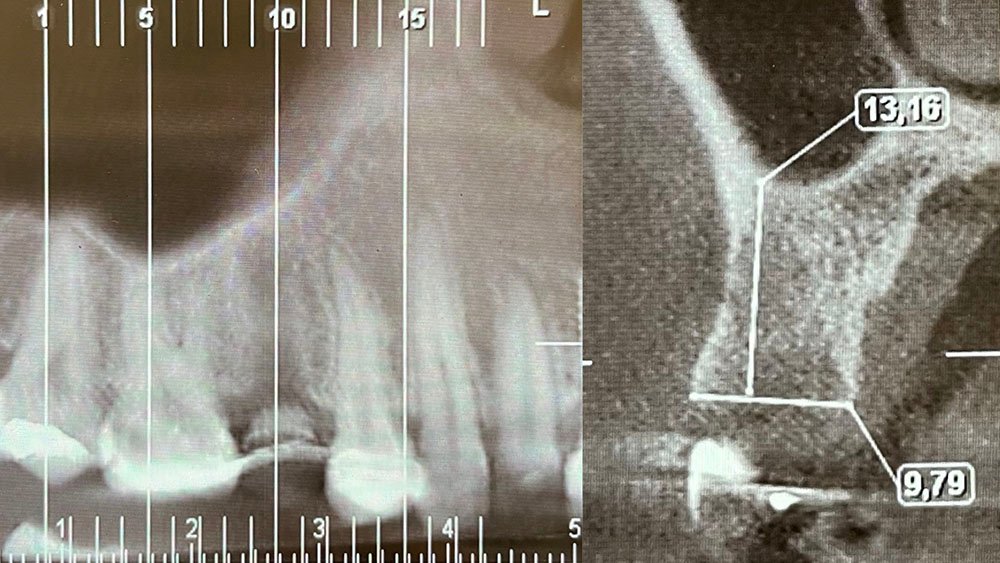

Para este relato de caso clínico selecionou-se a paciente A. S. P, do gênero feminino, de 22 anos, que procurou a Clínica de Especialização em Implantodontia devido a uma perda dentária do elemento 15 por trauma, culminando como queixa principal a ausência do elemento dental e a gengiva aprofundada.

Durante a anamnese, a paciente apresentou um bom estado de saúde geral e não relatou nenhum dado médico relevante que impossibilitasse o tratamento. No exame físico intraoral, observou uma boa condição de saúde bucal, notando-se apenas a ausência do elemento 15 com uma depressão óssea no vestibular. Dessa forma, objetivou-se um plano de tratamento baseado na utilização da técnica de rolo modificada e colocação de dente provisório.

No acompanhamento mensal realizou-se proservação e radiografias periapicais da região para verificar a cicatrização dos tecidos e integridade do implante. Após o período de três meses, foi cimentada uma coroa definitiva de zircônia monolítica.